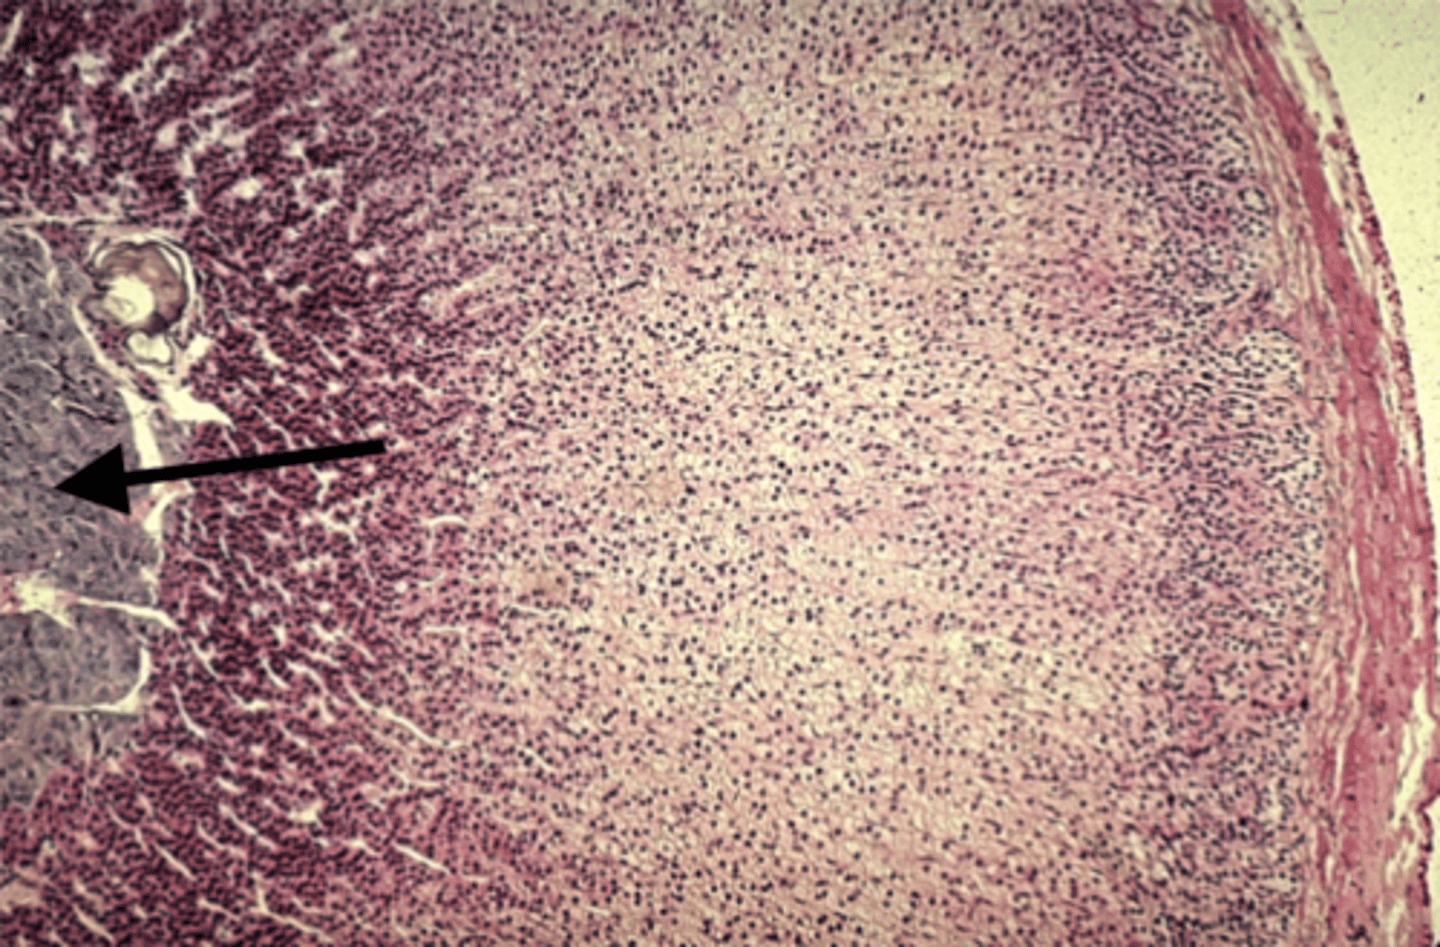

Adrenal gland

what is this?

Zona fasciculata

what is this pointing to?

Zona reticularis

what is this pointing to?

medulla

what is this pointing to?

Cortisol

Zona fasciculata secretes

Aldosterone

Zona glomerulosa secretes

Androgens

Zona reticularis secretes

Epinephrine

What hormone does the adrenal medulla secrete?